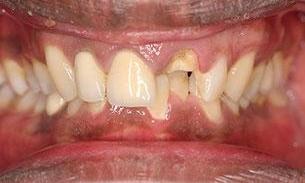

The patient wanted to be able to smile when she retires and travels around. An infected upper incisor was removed before a carefully designed ceramic bridge and a crown were placed. She was so thrilled with the result! Now she can show her teeth when she smiles in her photos.